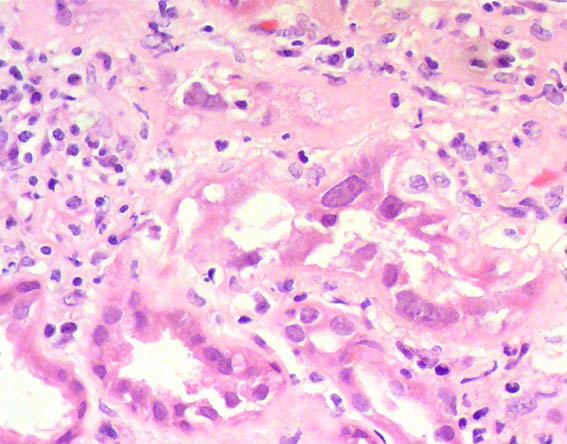

Figure 1. H&E, X100.

Figure 4. H&E, X400.

Figure 5. H&E, X400.